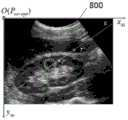

In one embodiment, as shown in FIG. 8, assume that theultrasound image plane 800 is taken as a frame of reference and the corresponding coordinate axis is xus,yus,zusWherein y isusI.e., V in fig. 7us-opt(i.e., the orientation of the ultrasound probe 102);

o: is the starting point of the planar frame of reference of the ultrasound image, i.e. P in FIG. 7us-optPoint P0 (the three-dimensional coordinates of the starting point of image acquisition of the ultrasound probe 102), and the size of theultrasound image plane 800 can be determined by the imaging depth, imaging resolution, and imaging size of theultrasound probe 102 in the three-dimensional calibration information;

Vnd-us: for the orientation of theneedle 101 in the ultrasound image plane frame of reference, V can be understood as the direction of the needlend-us=Vnd-opt-Vus-opt

T: for three-dimensional coordinates of the piercing tip in the planar frame of reference of the ultrasound image, i.e. P in FIG. 7nd-optPoint, can be understood as T ═ Pnd-opt-Pus-opt

T': projection of a puncture needle tip point T on an ultrasonic image plane;

TT': the position relation between the puncture needle point T and the projection T' thereof in an ultrasonic image plane reference system, and the length thereof is the offset distance of the puncture needle relative to an ultrasonic imaging plane;

ET': is the projection of the puncture needle in the plane of the ultrasonic image;

e: the intersection point of the projection of the puncture needle in the ultrasonic image plane and the edge of the ultrasonic image plane can be understood as the entry point of the projection ET' of the puncture needle into the ultrasonic image plane;

t' L: an extension line of the puncture needle projection ET';

l: the intersection point of the projection extension line T' L of the puncture needle and the edge of the ultrasonic image plane can be understood as the departure point of the projection of the puncture needle and the extension line EL thereof from the ultrasonic image plane;

EL: the projection of the puncture needle in the ultrasonic image and the extension line thereof are the track of the puncture needle in the ultrasonic image;

c: the intersection point of the puncture needle extension line and the ultrasound image plane is positioned on the puncture needle projection extension line T' L, as shown by a gray cross in FIG. 8;

TCT': in the ultrasonic image plane reference system, the angle value of the included angle between the puncture needle direction and the ultrasonic image plane is the offset angle of the puncture needle relative to the ultrasonic image plane;

a: a geometric central point of a puncture target region (such as a circular region in the figure) on an ultrasonic image plane, and coordinates of the puncture target region on the ultrasonic image plane are determined by image recognition (an initial position is marked by manual work, and then position tracking is carried out by the image recognition);

AT: in the ultrasonic image plane reference system, the position relation between the geometric center A of the puncture target area and the puncture needle point T is shown, and the length is the distance between the puncture needle point and the puncture target area.

As shown in fig. 9, the line segment ET 'and the line segment T' L form a track of the puncture needle in the ultrasound image plane, the cross C is the intersection point of the puncture needle direction and the ultrasound image plane, the curve M is the outline of the target puncture region, and the blob-like shadow in the outline is the puncture target. The current displayed picture is that the track (namely, the line segment EL) of the puncture needle in the ultrasonic image plane passes through a target puncture area (namely, the curve M), but the predicted position (namely, the cross mark C) of the puncture needle about to pass through the ultrasonic image plane is positioned outside the target area, so that the cross mark C can be kept in the target area (namely, the curve M) by adjusting the puncture needle, and the navigation can be completed by pushing the puncture needle until the cross mark C is coincided with the puncture needle tip (namely, T'), thereby realizing the successful puncture.